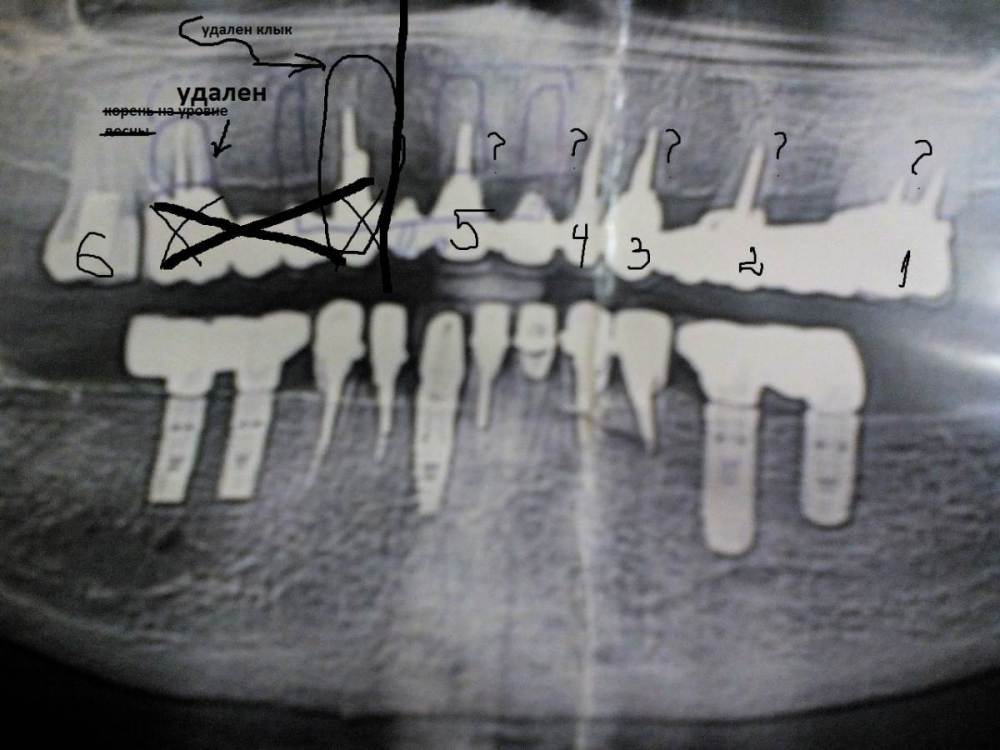

Ольга555 Опубликовано 28 июля, 2023 Поделиться Опубликовано 28 июля, 2023 Предложено полное удаление всех 6 корней и оставшейся мк конструкции, установка 6 имплантов Дентиум и открытый синус лифтинг с 2-х сторон на верхней челюсти. Все в один день. Мне 64 года. Временным, предложен съемный протез с началом изготовления через месяц. Расчет бюджетного протезирования. Смущает временная конструкция,не навредит она? Стоит ли изыскать дополнительные средства и рассмотреть другой способ протезирования на имплантах? И возможно ли вынести в один прием такой объем работы? Снимок 2-х летней давности.С диска КТ пока не знаю как скопировать. Фото эстетического состояния на сегодня.Почти год с отсутствующими. Ссылка на комментарий

Ольга555 Опубликовано 28 июля, 2023 Автор Поделиться Опубликовано 28 июля, 2023 2 года назад,когда мост подал сигнал готовиться к очередному этапу протезирования,как раз делала прикрепленный снимок и КТ для доктора,который ставил этот мост в конце 2010г. А через несколько месяцев он срезал конструкцию из-за образовавшегося флюса клыка(раскачала видимо подвижным мостом) и было новое КТ на половину ,где уже не было конструкции. План протезирования мне озвучил на 2 года работы ,8 имплантов , один синус лифтинг,временные сразу и стоимость почти 600 и предупредил о подорожании после НГ . Пока изыскивала возможности,заболела и кашляла около 3-х месяцев,потом СВО..а я из Курска,переживания что начнем процесс,а заканчивать может и не получится. Теперь боюсь узнать цену у своего прежнего доктора,доллар на взлете. Обратилась в другую частную клинику. Процесс более короткий 6 имплантов,два синус лифтинга открытых и работы чуть более пол года. Конечно трудно найти и принять решение. Ссылка на комментарий

Ольга555 Опубликовано 8 августа, 2023 Автор Поделиться Опубликовано 8 августа, 2023 Сегодня сходила на консультацию -новый вариант лечения... Очень сумбурно . Ортопед (по КТ совместная консультация с имплантологом) озвучил 6 имплантов дентиум. Закрытый синус лифтинг на 26. Мультиюнит на 15. Много непонятного,но объяснять мне подробно у ортопеда не было времени. Снять м\к мост 25авг.и сразу сделать такой же временный(не поняла смысла)? прикус29.08 1.09-не поняла что сделать..... 9.09- удалить 3 корня из 6-ти у хирурга и у ортопеда-сдача 14.10 -имплантация Спросила ,какую линейку дентиум будут использовать на верхней челюсти,ортопед сказал,что имплантолог решит какую...мне вникать не стоит. Корни все на удаление,но когда удалят оставшиеся 3... после имплантации?это нормально? Съемный протез на время приживления имплантов с крючками на неудаленных 3-х. так поняла. Но еще будет временный мост через 3 месяца на временных абатментах.... Имплантация 2-х этапная-классическая(через 6 недель после удаления). 16 исправлен на 15 установка имплата с мультиюнитом -не поняла(ошибка?) Мне не разобраться в этом каламбуре. Пожалуйста помогите,если возможно, хотя бы на выделенных вариантах. Прикрепляю все что у меня есть. КТ так и не поняла как прикрепить(попробую вникнуть еще раз). Можно ли ссылку на КТ в яндекс диске? Там папка со всеми файлами. Ссылка на комментарий